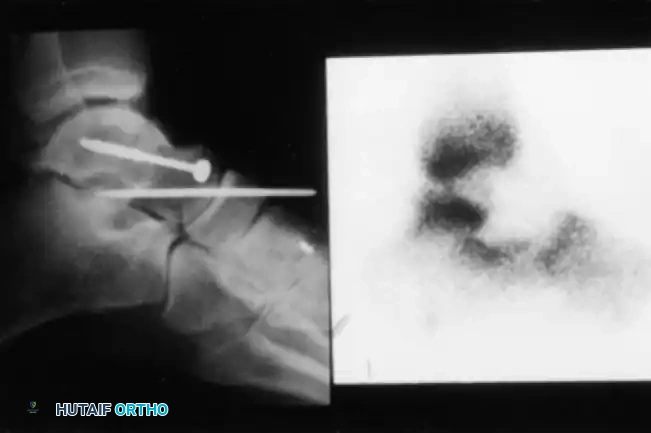

A critical prognostic indicator is the Hawkins sign—a subchondral radiolucency present in the talar dome 8 to 12 weeks after injury. This lucency represents subchondral osteopenia secondary to active hyperemia, indicating that the talar body remains vascularized.

Clinical Pearl: A positive Hawkins sign (subchondral lucency) at 12 weeks is a highly reliable indicator that osteonecrosis will not occur. Conversely, the lack of a subchondral lucency at 3 months strongly indicates that osteonecrosis has occurred.

Fig. 33-200 Hawkins line is not visible in sclerotic (latent osteonecrosis) talar dome 3 months after injury.

If standard radiographs are equivocal, bone scanning or Magnetic Resonance Imaging (MRI) may be utilized. Decreased uptake on a bone scan or altered signal intensity on MRI confirms the avascular state.

Fig. 33-201 Bone scan 8 days after open reduction of type IV talar neck fracture with talonavicular dislocation shows decreased uptake indicating area of osteonecrosis.